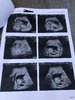

No hej, kamień z serca po tych prenatalnych. Cudowny widok. Moje dziecko chyba jest najbardziej ruchliwym dzieckiem na świecie! Haha cały czas tak brykało, ze szok. Machalo cały czas rączkami, nóżkami, np kładło się na brzuch i wypinalo pupę, a za chwile kic na plecy, tyle co fikołków zrobiło przy nas to szok. Widziałam jak buzie nawet otwiera i cały czas skakało i wierzgalo. Aż się dziwiłam, ze się nie meczy haha. Wszystko ok wg usg. Od główki do pupy ma już 7,56cm. Czy Wasze dziecko na prenatalnych tez tak szalało? :D nie jadłam nic słodkiego ani nic... ale byliśmy w szoku jak się rusza i takie piękne <3 a krwiaka nie było widać, wiec chyba zniknął :) spróbuje się powoli rozruszać, ale jeszcze 4go mam wizytę prywatnie u mojego gina i zobaczymy czy potwierdzi i oby mi leki w końcu zredukował. Ale dzisiaj szczęśliwy dzień :) w końcu... oby tak dalej.

Załączniki

• EB4BE8EC-2D53-4745-8B9D-AB17D944D679.jpeg

EB4BE8EC-2D53-4745-8B9D-AB17D944D679.jpeg

782,5 KB · Wyświetleń: 132

• D3CC77F3-648B-4C84-B6A8-214CB184F2BB.jpeg

D3CC77F3-648B-4C84-B6A8-214CB184F2BB.jpeg

682 KB · Wyświetleń: 137